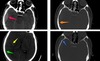

Label the types of extra-axial bleed occuring at the red; yellow & green arrows [3]

**red arrow: EDH** brown arrow shows how EDH respects the suture margins **yellow arrow points at SAH** **green arrow: SDH** blue arrow shows the fracture